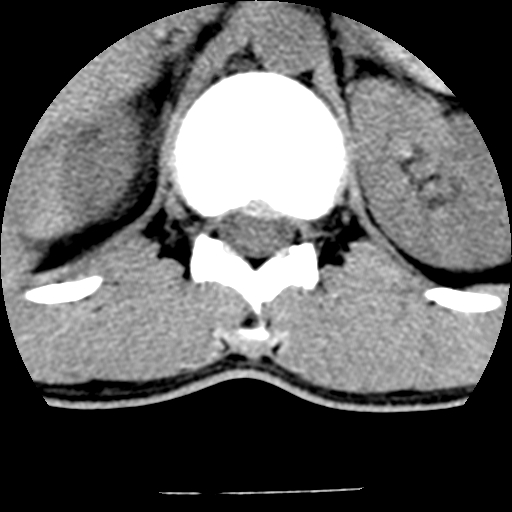

男,31岁,从6米高处坠落伤两天,腰背部疼痛,临床要求ct扫描胸10-腰1。请大家帮忙看看骨质有问题吗?

t12、l1锥体前缘轻度楔形变,平扫示椎体前缘骨小梁欠规整,第9幅图示椎体前缘骨质不连续,结合外伤史考虑椎体轻度压缩骨折。

楼主扫描层厚可能较大,每个椎体只有三个层面.

从所示层面分析,无明确骨折征象,象类似病人我个人会建议mri除外骨挫伤.

从上查骨窗第九片椎体前缘皮质显示断裂.压缩骨折?